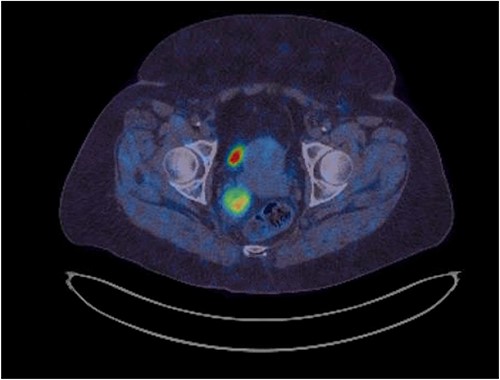

Her physical exam was normal. A right extraluminal mass was barely palpable on digital rectal examination. The pararectal mass showed no hypermetabolic activity on recent positron emission tomography (PET) scan. Either a GIST or a NET was suspected. Gallium-68 Dotatate PET scan revealed high expression of somatostatin receptors (Fig. 2). Pelvic magnetic resonance imaging (MRI) showed an isodense lesion, slightly heterogenous, on T1-weighted images with persistent T2 hyperintensity and restricted diffusion (Fig. 3). It was infiltrating the right lateral mesorectum without direct contact with the rectal wall. Colonoscopy showed no endoluminal lesion. Two ultrasound-guided fine needle aspirations (EUS-FNA) were unconclusive and patient developed osteodiscitis. Transgluteal CT-guided biopsy finally revealed the presence of thyroid tissue. Listed diagnoses were teratoma, tailgut cyst, or less likely, thyroid carcinoma. Subsequent thyroid ultrasonography revealed four non-specific micronodules. Thyroid function tests were normal, except for primary hyperparathyroidism. Parathyroid sestamibi scan suggested a single adenoma. A multidisciplinary team was made up of colorectal, head and neck, and orthopedic surgeons, along with an endocrinologist. The case was discussed at the Colorectal Tumor Board. A collaborative two-step surgical approach was proposed.